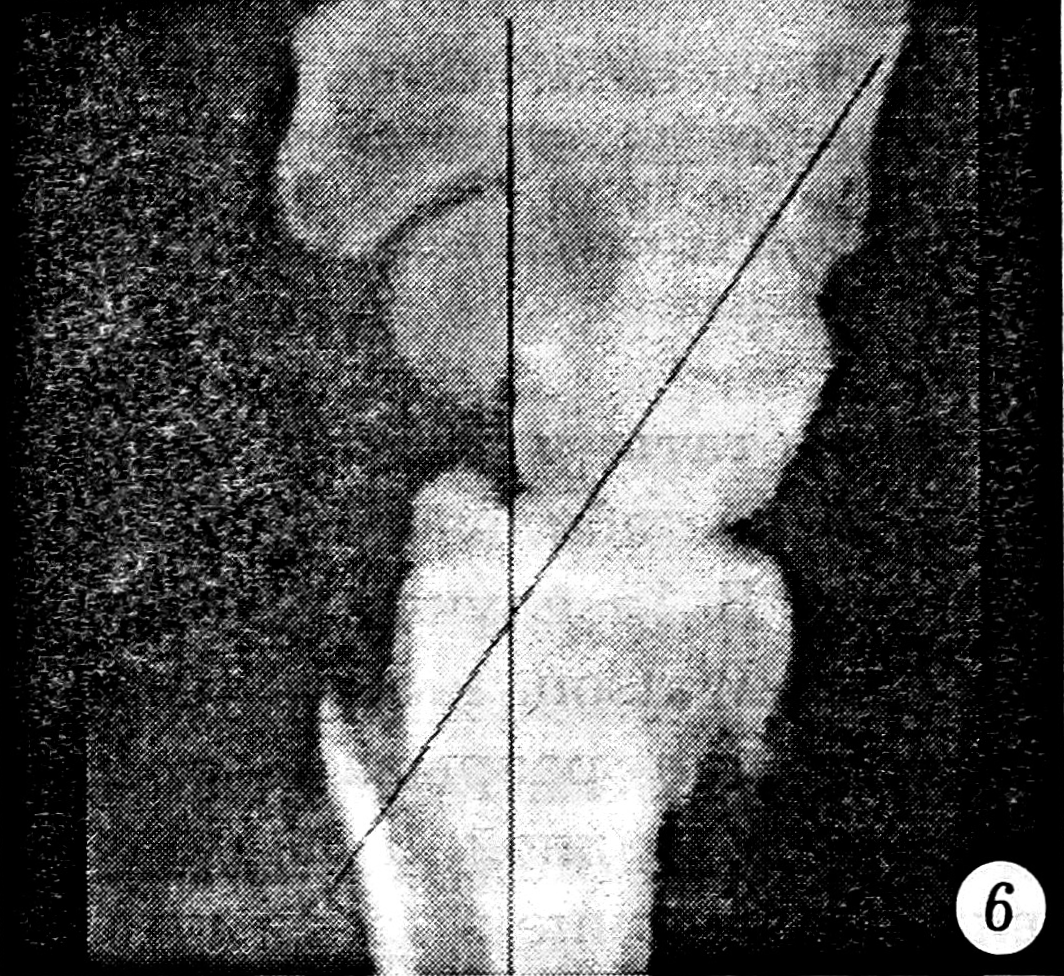

Исследовались первичные рентгенограммы и контрольные, сделанные после выполнения репозиции. Отбирались те случаи, в которых хотя бы на одном снимке присутствовали один или несколько из следующих рентгенологических признаков повреждения межзапястных связок: увеличение полулунно-ладьевидного угла более чем до 70° (рис. 1), симптом «кольца» дистального полюса ладьевидной кости (рис. 2), изменение формы и расширение полулунно-ладьевидного промежутка до 3 мм и более (рис. 3), нарушение непрерывности трех «запястных арок» (рис. 4), расширение полулунно-трехгранного промежутка (рис. 5) и увеличение полулунно-головчатого угла более чем до 20° (рис. 6) [5]. Результаты исследования представлены в табл. 1.

Рис. 6. Увеличение полулунно-головчатого угла свыше 20°.

Достоверной оказалась разница в значениях двух последних из представленных в табл. 2 характеристик. Более того, полулунно-головчатый угол превышал 20° у 9 из 17 больных с нестабильным и только у 2 из 15 со стабильным суставом. Из 5 пациентов с положительным тестом Reagan у 4 полулунно-трехгранный промежуток был более 3 мм.

Результаты проведенного исследования свидетельствуют, что наиболее достоверными для постановки диагноза острого разрыва межзапястных связок при переломе лучевой кости в «типичном месте» являются: величина полулунно-головчатого угла более 20°, расширение полулунно-трехгранного промежутка до 3 мм и более и увеличение полулунно-ладьевидного угла более чем на 10° после репозиции перелома.